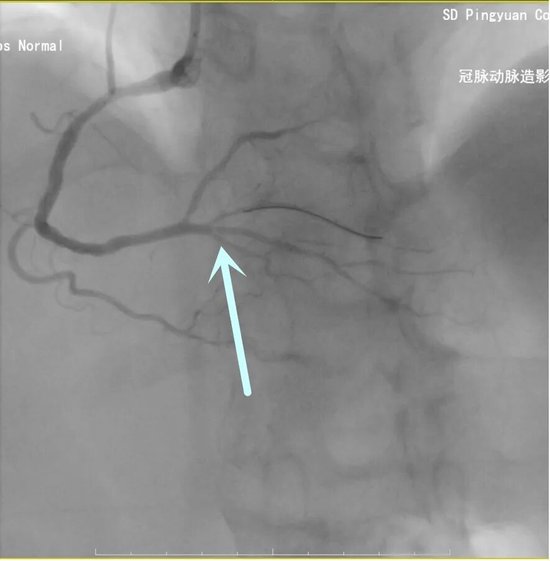

61岁的王先生因“阵发性上腹部不适”就诊,检查发现竟是凶险的急性前壁心肌梗死。择期冠脉造影结果让在场的医生都捏了一把汗:左主干+三支病变。这意味着患者的心脏供血,如果不及时干预,随时可能发生猝死。

面对这一介入领域的“硬骨头”,平原县人民医院心内科团队迎难而上,在左主干-前降支的关键病变处精准植入支架。术后造影显示,狭窄解除,血流恢复,患者转危为安。这例手术的成功,标志着该科在处理复杂高危冠脉病变方面达到了一个新的技术高度。